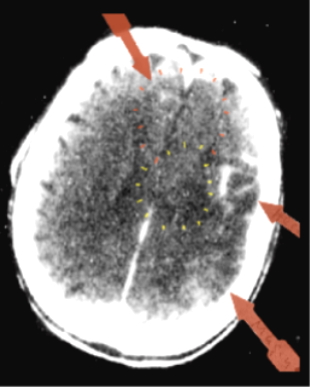

Der erste entdeckte „Hamersche Herd“

Bereits 1982 gelang es mir – also ein Jahr nach der Entdeckung der Germanischen Heilkunde (damals noch „Eiserne Regel des Krebs“) – schon prospektiv einen Hamerschen Herd (HH) riesigen Ausmaßes bei einem Patienten mit Revierkonflikt in der Heilungsphase und Herzinfarktgeschehen in der epileptoiden Krise zu finden.

Von da ab wusste ich, dass es keine Hirntumoren gab, sondern dass diese Phänomene alle im Zusammenhang mit der Lösungsphase eines biologischen Konfliktgeschehens stehen mussten.

Der Patient, zu dem diese Bilder gehören, war der allererste, bei dem ich prospektiv einen später sog. „Hamerschen Herd“ suchte und auch fand.